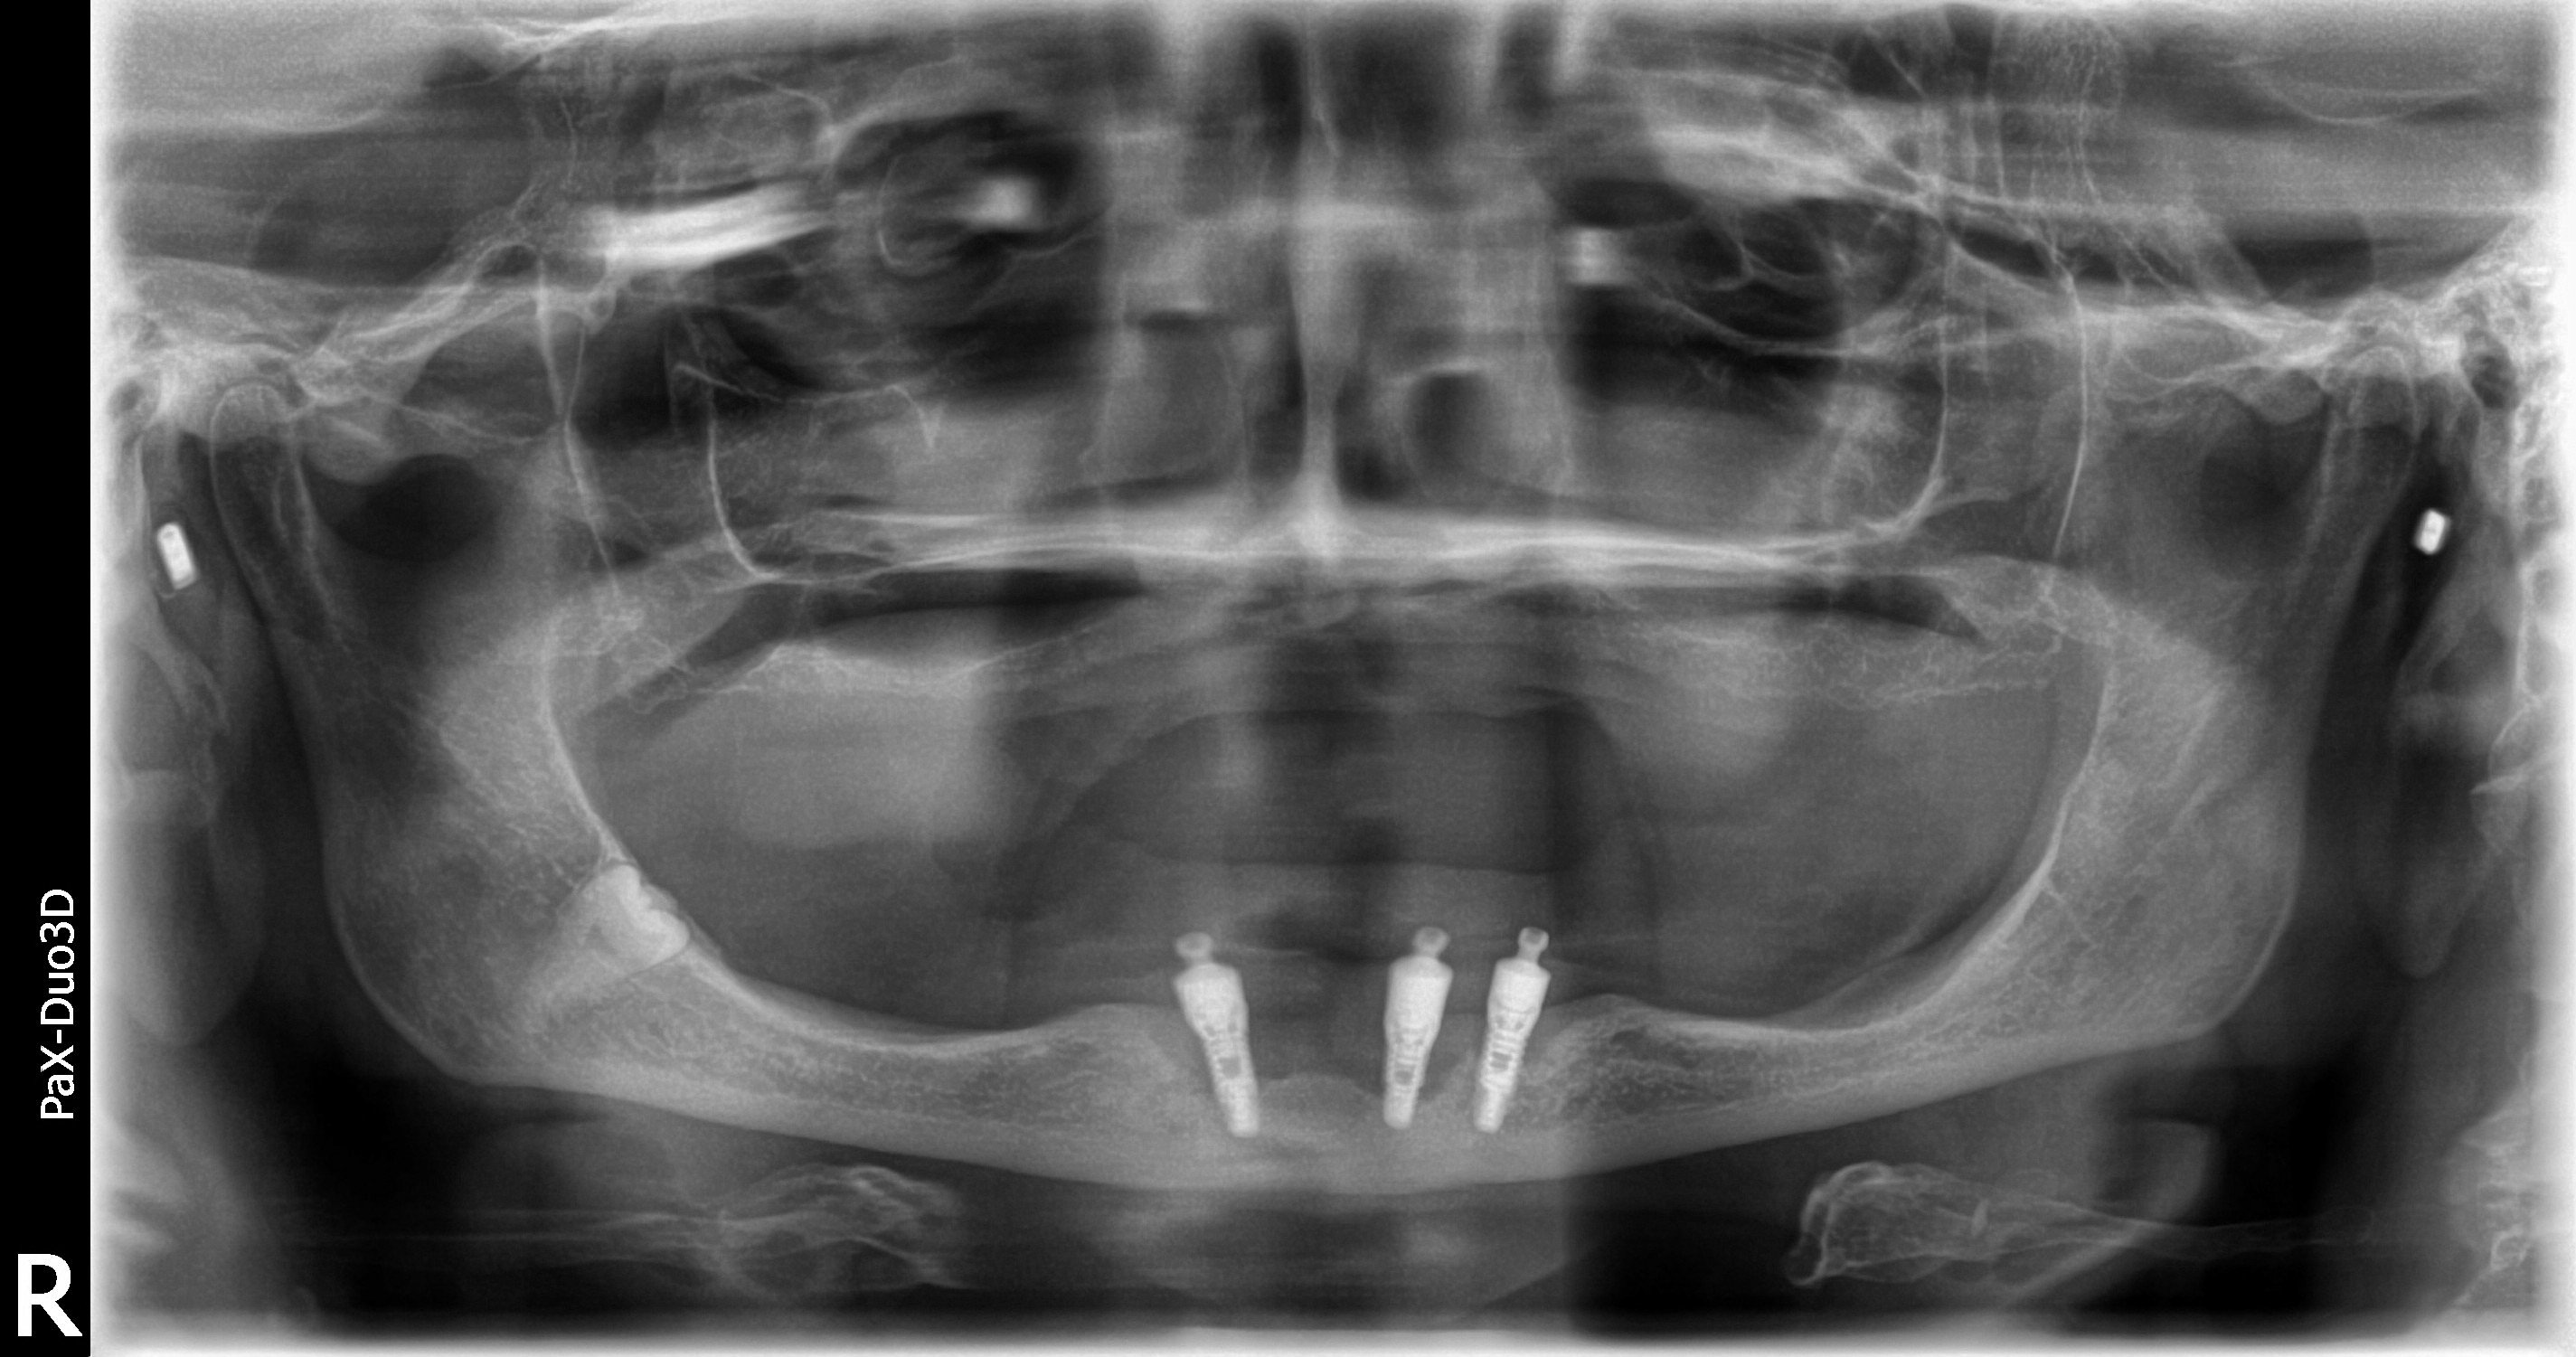

Patient 7 xray of bone graft and 4 dental implants (the image does Dental Bone Graft Failed Twice What causes a dental bone graft to fail? Patients who are about to undergo dental treatment, especially surgery,. If you are experiencing early failure, you will see signs in about three to four months after you have had your surgery. There are different stages of failed dental implants, early and late. In this article, we will explore the warning signs. Dental Bone Graft Failed Twice.